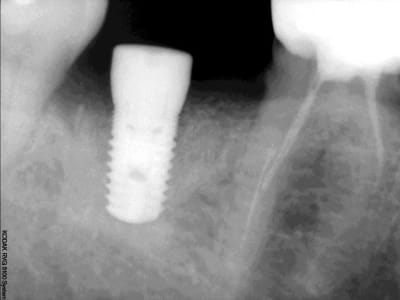

J'ai mis il y a de ca 1 mois 1 implant en position de 46 de 6 mm de diametre et de 8 mm de long car proche du nerf.

Au bout de 1 mois à la radio retroalveolaire je n'ai pas d'image qui me laisse penser un rejet ,ni meme de douleur.Mais l'implant bouge ?

peux tu nous mettre ta radio pour t'en dire un peu plus...

radiologiquement as tu un contact intime (petite fibrose asymptomatique pour le patient mais ton implant bouge) en fait on ne sait jamais quel pourcentage de la surface s'ostéointègre ...

quelle que soit nos considérations vu la longueur de l'implant tu pousse 1/3 de carpule et il va monter es tu sur de ne pas pouvoir mettre plus long ta rvg est franchement moyenne as tu utilisé l'export du logiciel kodak ?

d'accord avec chicot,remettre implant plus mesial,et d'apres les apexs des dents voisines tu peux en mettre un plus long

et le scan ? tu sembles avoir de la hauteur pourtant ?

> non c'est du 5 mm

il me semblait bien !!! pourtant tu avais dit du 6 mm !!!??? n'aurais-tu point sur-foré ?

qqch me dit que tu as été trop fort dans ton forage et avec du 8 de long ça ne pardonne pas...

de plus tu te dis proche du nerf mais ta radio montre que tu peux au moins mettre du 11,5 mm

tu vas donc redescendre à 10 mm de profond avec tes forêts pour un diamère crestal de 5 , bien gratter tes parois et poser un diamètre 6 par 11,5 par exemple, vis de fermeture, sutures.

A mon avis tu n'avais pas beaucoup de hauteur et une crete large, et ton implant est cratérisé tout autour et tu voi a la radio les corticales. dc radiologiquement ca va mais tu as une conque fibreuse autour